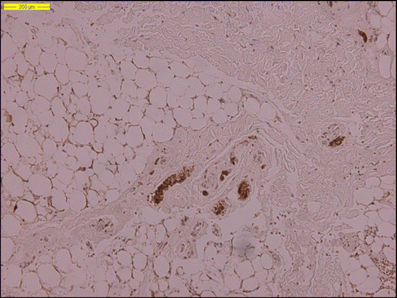

Histological examination of the resected stalk revealed connective tissue, of which some parts were positively stained with epithelial membrane antigen (EMA), indicating a dural origin. A considerable amount of fat and large vessels were seen. The absence of a lumen in the resected stalk was confirmed (Fig. 5a, b).

Fig. 5

figure 5

Photomicrographs of the resected stalk in case 2. Some areas are EMA positive (a). Note the large vessels and a considerable amount of fat (b)